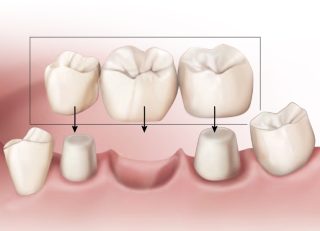

Bridge